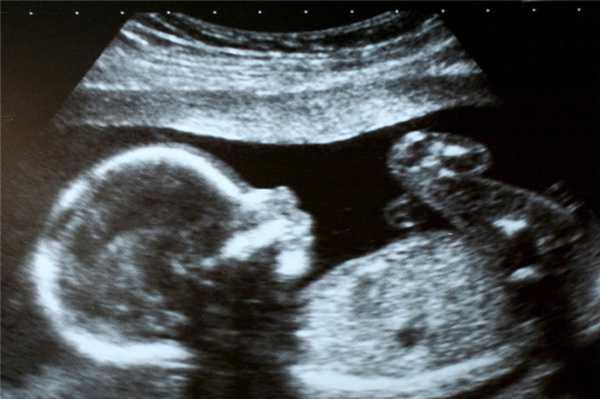

Фото УЗИ ребенка на разных сроках беременности

Если беременность желанная, будущие родители внимательно относятся к пренатальной диагностике плода. Чтобы убедится, что ребенок развивается нормально, в течение 9 месяцев гинеколог несколько раз направляет женщину на ультразвуковое исследование. Фото УЗИ может многое рассказать врачу и будущим родителям о малыше. Кроме того, снимок станет трогательным напоминанием для семейного архива.

Чтобы сделать фото УЗИ малыша на разных сроках, беременной женщине необходимо записаться на ультразвуковой скрининг в медицинском центре «Диана».

- 3D УЗИ . В этом случае картинка более качественная, объемная и цветная. Так как на фото хорошо видны все детали, удается рассмотреть особенности внешности и даже выражение лица малыша. Однако процедура займет почти час.

3D и 4D УЗИ целесообразно проходить только во втором и третьем триместре.